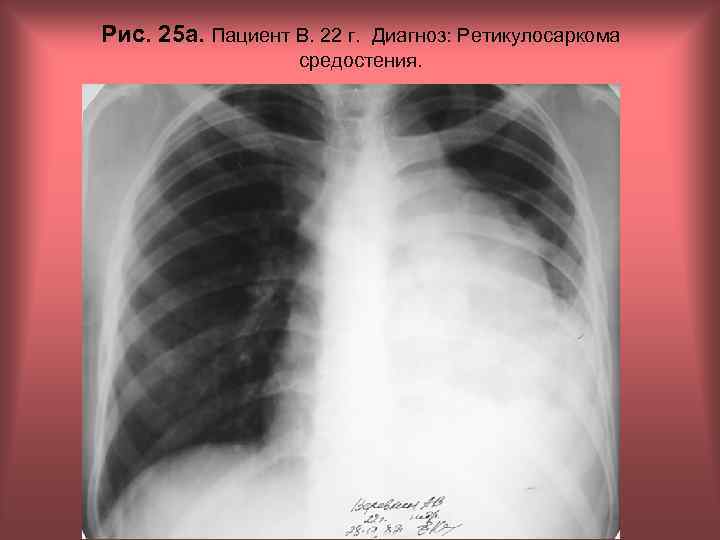

Рис. 25 а. Пациент В. 22 г. Диагноз: Ретикулосаркома средостения. Н. С. Воротынцева, С. С. Гольев Рентгенопульмонология